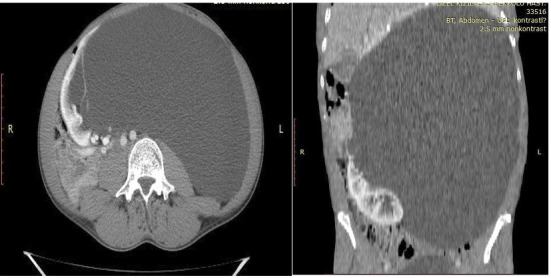

Simple renal cysts are the most common cystic abnormalities of the kidney, typically observed in older individuals and often asymptomatic, requiring no treatment. These cysts are usually detected incidentally during imaging for unrelated conditions. Giant renal cysts, defined as those exceeding 15 cm in diameter and containing over 1500 mL of serous fluid, are exceptionally rare. We report a case of a 34-year-old male presenting with a rapidly growing giant renal cyst (40 × 28 cm) in the left kidney, resulting in malnutrition and significant weight loss. The patient underwent successful laparoscopic transperitoneal cyst excision. At the 1-year follow-up, the patient was asymptomatic, with no evidence of residual cyst recurrence.

单纯性肾囊肿是最常见的肾脏囊性异常,通常在老年人中观察到,通常无症状,无需治疗。这些囊肿通常是在成像时偶然发现的。巨大肾囊肿,定义为直径超过15cm,含有超过1500ml浆液的囊肿,极为罕见。我们报告一例34岁男性左肾出现快速生长的巨大肾囊肿(40 × 28 cm),导致营养不良和体重明显下降。患者接受了成功的腹腔镜经腹腔囊肿切除术。随访1年,患者无症状,无残留囊肿复发迹象。